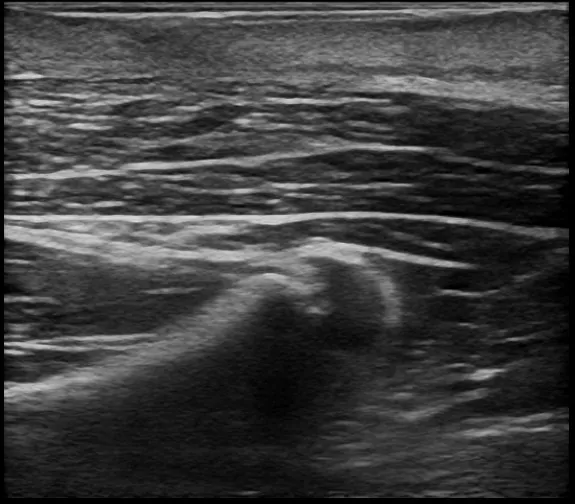

徐々に皮下腫瘍が大きくなったため、当院を受診されました。左肩に120mm大の巨大な皮下腫瘍があり、超音波検査の結果、典型的な粉瘤と診断されました。

術前